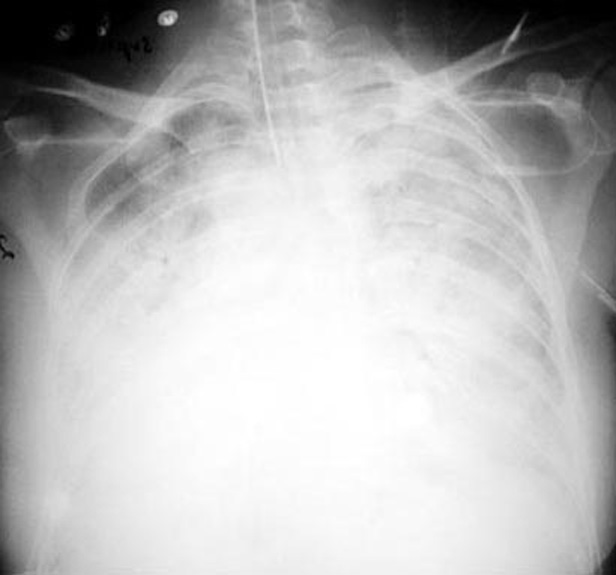

Total atelectasis of Lung

The right hemi thorax is whited out (no air).

Signs of loss of lung volume include:

• Trachea is shifted to the right (yellow arrow)

• Hemi thorax is smaller on the right

• Crowding of ribs on the right

Silhouette sign:

The silhouette of the right heart and right hemi diaphragm are lost.

Vessels in right lung not seen due to loss of air in alveoli